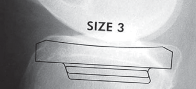

القوالب المسبقة (Preoperative Templating):

يتم استخدام الأشعة السينية لتحديد حجم وموضع المكونات المزروعة بدقة قبل الجراحة.